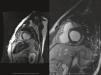

Late gadolinium enhancement (LGE) cardiac magnetic resonance imaging (MRI) is very useful in distinguishing between myocardial infarction, in which the enhancement is typically subendocardial, and myocarditis, in which it is subepicardial (Figure 1). In addition, various patterns have been described with different cardiomyopathies, in some cases enabling a specific diagnosis without invasive workup and risk stratification.1 Cardiac amyloidosis was previously thought to be present only when systemic amyloidosis was patently manifest. This has proved not to be the case, with cardiac MRI detecting increasing numbers of cases in patients with diastolic heart failure in whom cardiac involvement may be the first or sole manifestation. The pattern of LGE commonly found in cardiac amyloidosis is a global subendocardial enhancement with different contrast kinetics, the ventricular cavities showing no signal at all (Figures 2–6) compared to myocarditis and acute myocardial infarction, in which there is an intracavitary gray signal (Figure 1). Of 10 patients referred after echocardiography raised the suspicion of a cardiomyopathy, five were diagnosed with cardiac amyloidosis, two had images not suggestive of amyloidosis and were subsequently found to have Fabry's disease (Figure 7), and the other three probably had concentric left ventricular hypertrophy due to hypertension.